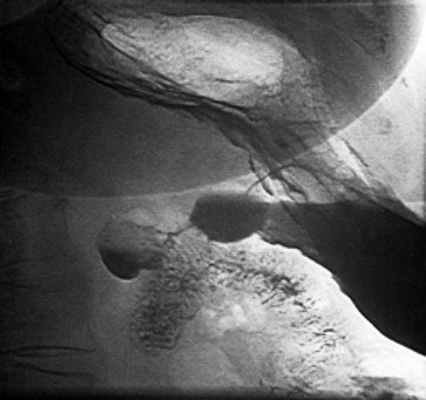

При рентгеноскопии желудка и двенадцатиперстной кишки: акт глотания не нарушен. Пищевод свободно проходим, определяется значительных размеров (до 7 см) грыжа пищеводного отверстия диафрагмы с выраженным рефлюкс-эзофагитом и забросом содержимого желудка в дистальный отдел пищевода, увеличивающаяся в размерах в положении лежа на животе. Желудок обычно расположен, натощак содержит слизь и жидкость. Складки слизистой утолщены, извиты, по задней стенке и большой кривизне в кардиальном отделе образуют зубчатость. Привратник свободно проходим, отмечается пролабирование слизистой желудка в луковицу двенадцатиперстной кишки. В нисходящей ветви петли двенадцатиперстной кишки определяется дивертикул на ножке размером 3 см с большим количеством слизи в нем (рис. 2). Луковица двенадцатиперстной кишки раздражена, бариевая взвесь очень быстро проходит ее, отмечается обратный заброс бариевой массы в желудок. Заключение: скользящая грыжа ПОД. Рефлюкс-эзофагит. Гастрит. Дуоденит. Дуоденогастральный рефлюкс. Дивертикул петли двенадцатиперстной кишки с признаками дивертикулита. От проведения ЭГДС пациентка категорически отказалась.

![Рентгенограмма дивертикула петли двенадцатиперстной кишки]()

Рис. 2. Рентгенограмма дивертикула петли двенадцатиперстной кишки.